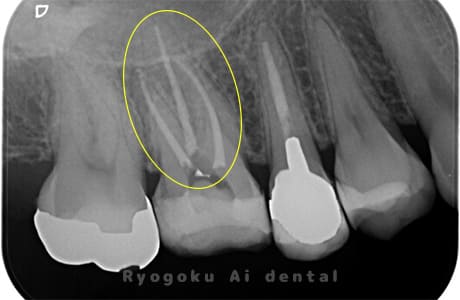

Case05

-

- 原因

- 慢性根尖性歯周炎

- 治療内容

- マイクロエンド

- 治療費用

- 121,000円(被せ物は含まない)

他院ではお薬の交換と抗生剤の処方で経過を診ていた患者さんです。歯茎の腫れが治らないとのことで、根管治療を開始し、2回目のご来院で腫れが引いたケースです。現在は被せ物も入り、良好に経過しております。

<リスク・副作用>

術後は痛み、腫れ、痺れなどの副作用が生じる場合があります。症状が再発する可能性があります。